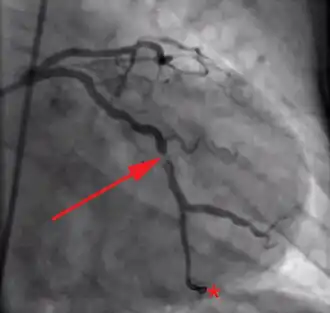

The concept of reperfusion has become so central to the modern treatment of acute myocardial infarction, that we are said to be in the reperfusion era.[53][54] Patients who present with suspected acute myocardial infarction and ST segment elevation (STEMI) or new bundle branch block on the 12 lead ECG are presumed to have an occlusive thrombosis in an epicardial coronary artery. They are therefore candidates for immediate reperfusion, either with thrombolytic therapy, percutaneous coronary intervention (PCI) or when these therapies are unsuccessful, bypass surgery.

Individuals without ST segment elevation are presumed to be experiencing either unstable angina (UA) or non-ST segment elevation myocardial infarction (NSTEMI). They receive many of the same initial therapies and are often stabilized with antiplatelet drugs and anticoagulated. If their condition remains (hemodynamically) stable, they can be offered either late coronary angiography with subsequent restoration of blood flow (revascularization), or non-invasive stress testing to determine if there is significant ischemia that would benefit from revascularization. If hemodynamic instability develops in individuals with NSTEMIs, they may undergo urgent coronary angiography and subsequent revascularization. The use of thrombolytic agents is contraindicated in this patient subset, however.[55]

The basis for this distinction in treatment regimens is that ST segment elevations on an ECG are typically due to complete occlusion of a coronary artery. On the other hand, in NSTEMIs there is typically a sudden narrowing of a coronary artery with preserved (but diminished) flow to the distal myocardium. Anticoagulation and antiplatelet agents are given to prevent the narrowed artery from occluding.